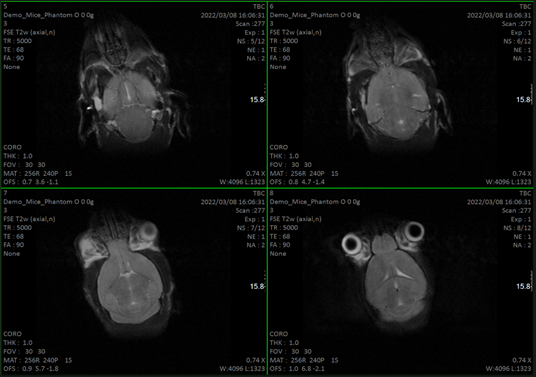

- Qualitative and quantitative studies (relaxation times T1 and T2 and even making maps) at the brain level and other organs.Cardiological sequences: diffusion, determination of blood volume…

- Oncological studies to detect and locate tumors and volume calculation.